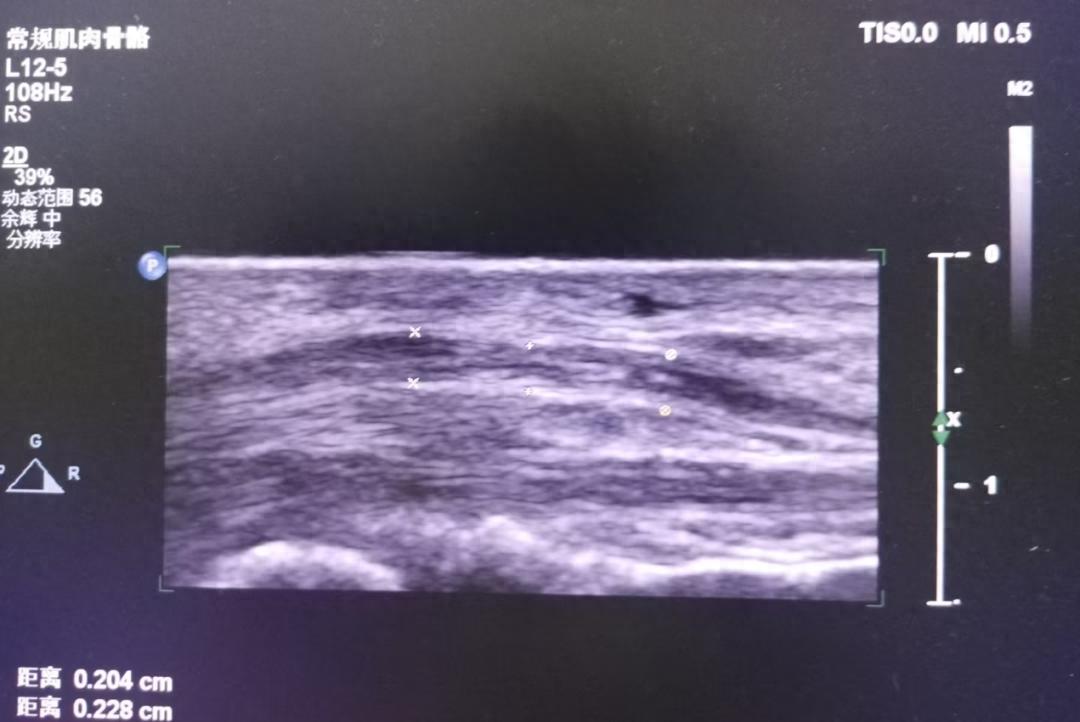

接诊医生详细询问了大姨的病情,并进行了全面的检查。在排除了其他可能的原因后,医生建议大姨进行超声检查。超声科主任毕晓芳利用肌骨超声对大姨的手腕部进行了精准检查,通过超声动态成像技术,清晰观察到:

✓ 腕管内神经水肿信号

✓ 肌腱滑动受限轨迹

✓ 局部炎性渗出情况

腕横韧带增厚压迫正中神经(腕管综合征)

拇长展肌腱鞘腔隙狭窄(桡骨茎突狭窄性腱鞘炎)